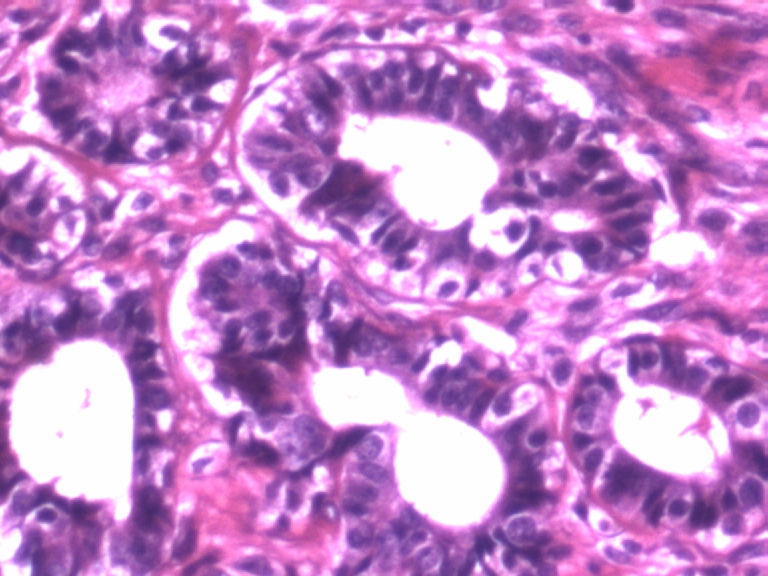

• 乳腺肿物图1

图1

患者,女,29岁,右侧乳腺肿物一个月。切面淡黄,均匀一致,质中。

标签:乳腺管状腺瘤

病变组织小叶结构未见,见管状、盲管状的腺管,周围似有空亮的肌上皮,腺上皮可见细小的核仁,染色质均细,导管上皮普通型增生。有包膜为盲管状腺瘤,则为腺病。

本例似乎有肌上皮存在,那就可能是良性的,如果有包膜就是腺瘤,管状腺瘤。

肌上皮可见,导管不规则,细胞有异性,极性还可。有核仁,考虑乳腺腺病,部分腺体呈不典型增生。